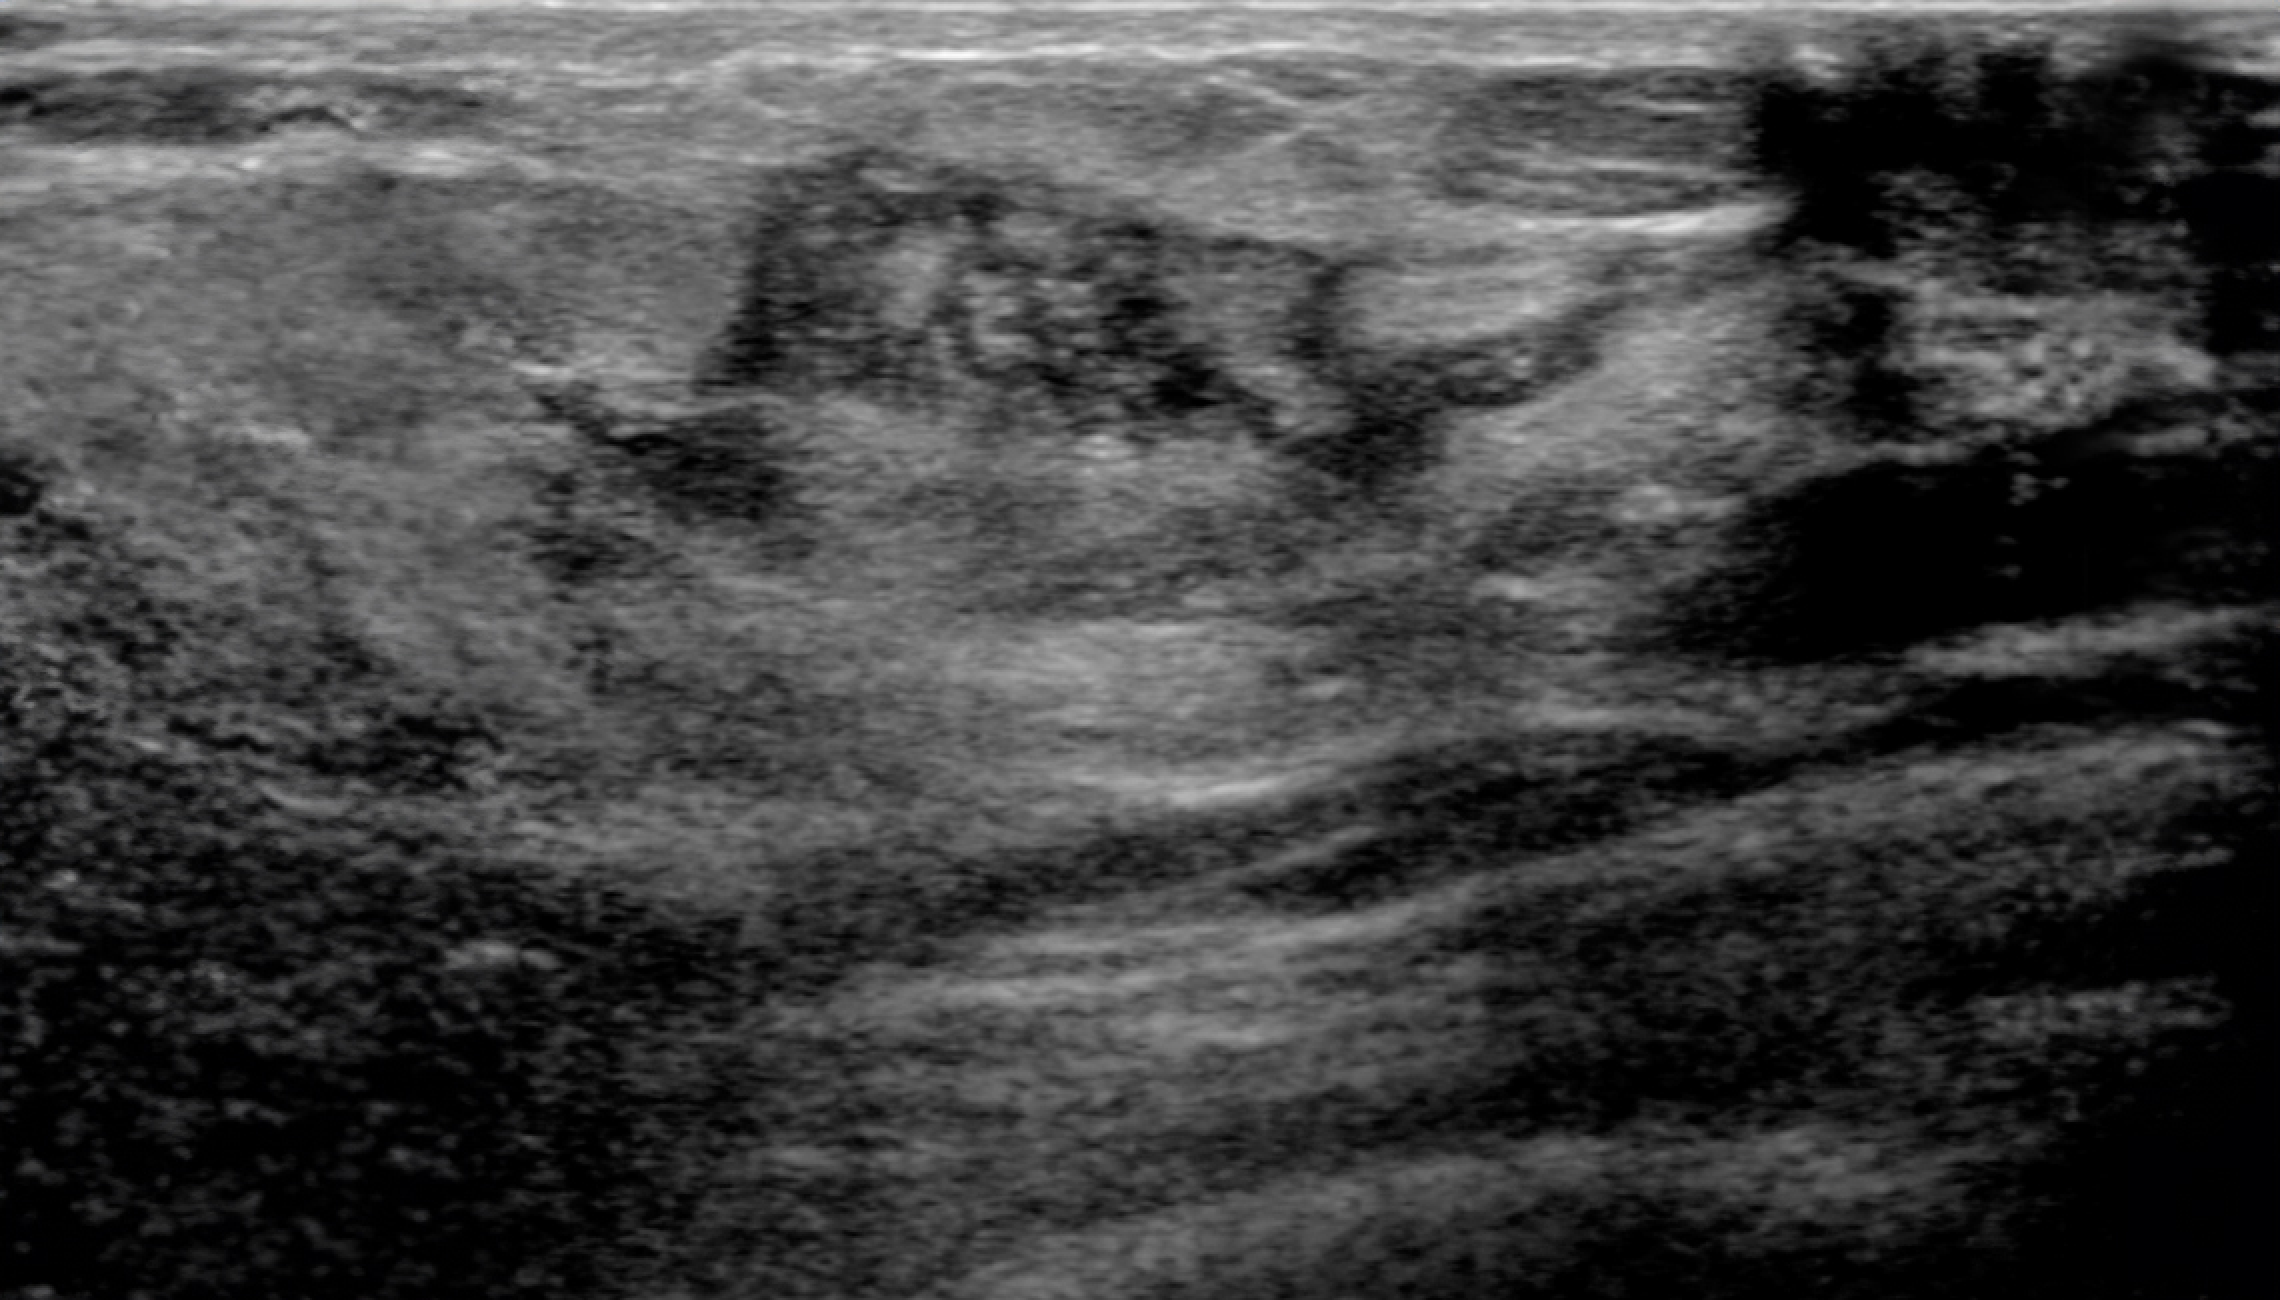

Automatic Detection of Abnormal Lesions

Automatically detects the locations of abnormal lesions in breast ultrasound images in real time.